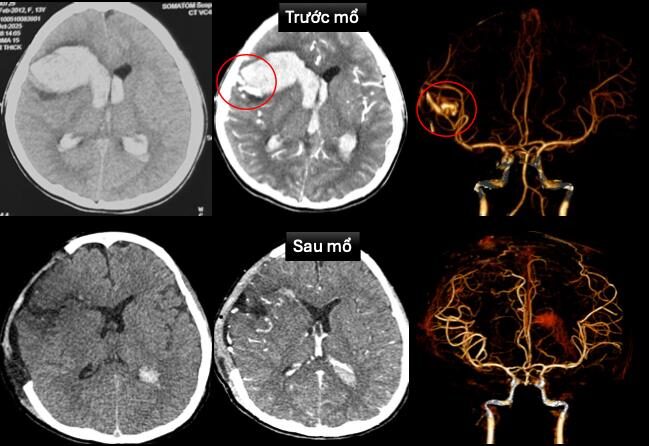

Tại Bệnh viện Nhi Đồng 1, bệnh nhi được ghi nhận hôn mê sâu, thở máy, mạch chậm, huyết áp tụt, đang duy trì thuốc vận mạch. Ekip lập tức siêu âm tim và chụp cắt lớp vi tính não cấp cứu, dựng hình mạch máu để xác định nguyên nhân. Kết quả cho thấy bé bị vỡ dị dạng động – tĩnh mạch trán phải, gây xuất huyết nhu mô não lan vào hệ thống não thất, kèm sốc tim, rối loạn nhịp và bệnh cơ tim xốp – một bệnh lý cực hiếm, đặc trưng bởi cấu trúc cơ tim có nhiều hốc sâu bất thường.

Hình ảnh chụp cắt lớp vi tính sọ não và dựng hình mạch máu não trước và sau mổ

Trước tình huống “ngàn cân treo sợi tóc”, bệnh viện đã kích hoạt hội chẩn đa chuyên khoa. Các bác sĩ tim mạch can thiệp đặt máy tạo nhịp tạm thời để duy trì nhịp tim, trong khi ekip ngoại thần kinh khẩn trương mở sọ giải áp, vi phẫu cắt bỏ dị dạng mạch máu và lấy máu tụ trong não. Sau phẫu thuật, bệnh nhi được chuyển đến khoa Hồi sức Ngoại để tiếp tục điều trị tích cực bằng thở máy, thuốc vận mạch và chống phù não.

May mắn, sau nhiều ngày theo dõi sát sao, tình trạng bệnh nhi cải thiện rõ rệt: tim mạch ổn định, rút được máy tạo nhịp, ngưng thuốc vận mạch; hiện bé đã tỉnh, có thể giao tiếp, chỉ còn yếu nhẹ chân phải. Hình ảnh chụp cắt lớp vi tính sau mổ không còn ghi nhận dị dạng mạch máu não, chức năng tim được cải thiện đáng kể với chỉ số EF tăng lên 65%.